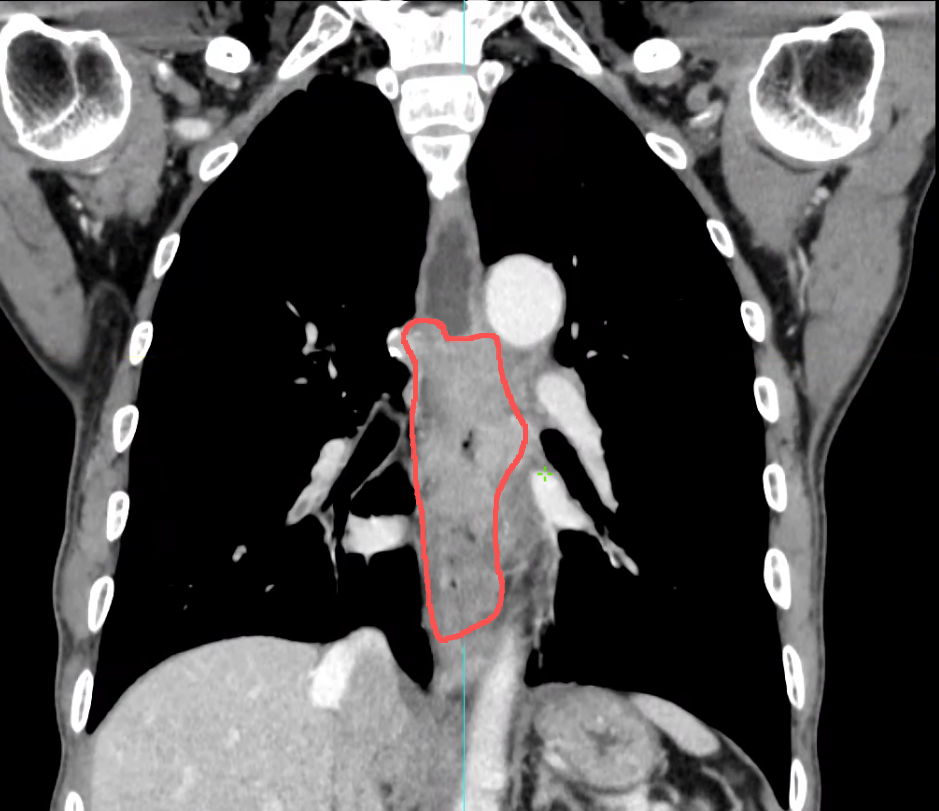

随后再通过CT扫描提供3D的全息地图,它能清晰勾勒出胃壁与腹壁最贴合的那个安全窗口,让医生能避开所有危险,选中那条唯一的最佳路径。

第一步,让胃部充盈起来,长期无法进食会导致胃腔完全皱缩,无法获取足够的操作空间。于是在DSA的监视下,通过预先建立的通道,医生向王老的胃里注入了600ml空气。原本干瘪的胃腔像一个慢慢吹起的气球,稳稳地贴住了前腹壁。把游移不定的移动靶,变成了一个轮廓清晰的固定靶。

第二步,固定胃壁。患者被平稳转移到CT机上,扫描确认后,朱柏霖医生使用造瘘套件中的巧妙装置,在选定的穿刺点周围,像打两颗精密的膨胀螺丝一样,将胃壁和腹壁轻柔而牢固地缝合在一起。

最后,再次扫描CT,屏幕上清晰显示:造瘘管头端完美位于胃腔中心。手术顺利完成,留下的创口,仅有一个不大的针眼。而王老的腹壁上,则多了一根柔软的管子,对他而言是重新接通的命脉,一两天后王老就能通过这根管子正常的进食食物,这不仅是能量的输送,更是生活尊严的回归,他得以摆脱鼻饲管的纠缠与窘迫,以更舒适更体面的姿态,储备力量,直面接下来的抗癌治疗。